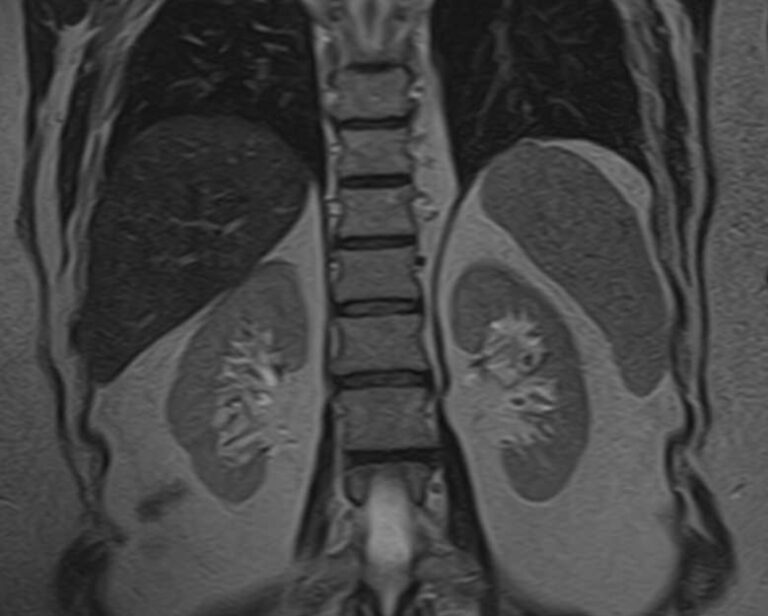

Магнитно-резонансная томография селезенки – высокоинформативный метод исследования органа с использованием внешнего магнитного поля, который позволяет с высокой точностью и достоверностью оценить структуру органа, его размеры, расположение, состояние сосудистой системы и паренхимы селезенки, а также окружающих тканей. МРТ селезенки часто применяется при гематологических заболеваниях, в онкологии, иммунологии.

МРТ селезенки: что показывает

• Новообразования (гемангиомы, саркомы и др.) и метастазы

• Повреждения селезенки (гематомы)

• Сосудистые нарушения (инфаркт, тромбоз вены селезенки, аневризма селезеночной артерии)

• Увеличение селезенки (при портальной гипертензии, болезни Гаучера и т.д.)

• Воспалительные процессы (абсцессы, саркоидоз, гистоплазмоз и др.)

• Кисты селезенки

• Признаки гематологических заболеваний

• Аномалии развития (добавочная селезенка и т.д.)